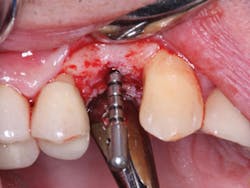

12. The lab will make the guide and send it to you (figures 1 and 2).

Figures 1 and 2:

The lab has made a printed surgical guide for a specific case. The designated drill is easily related to the guide and provides near-perfect placement of the implant.